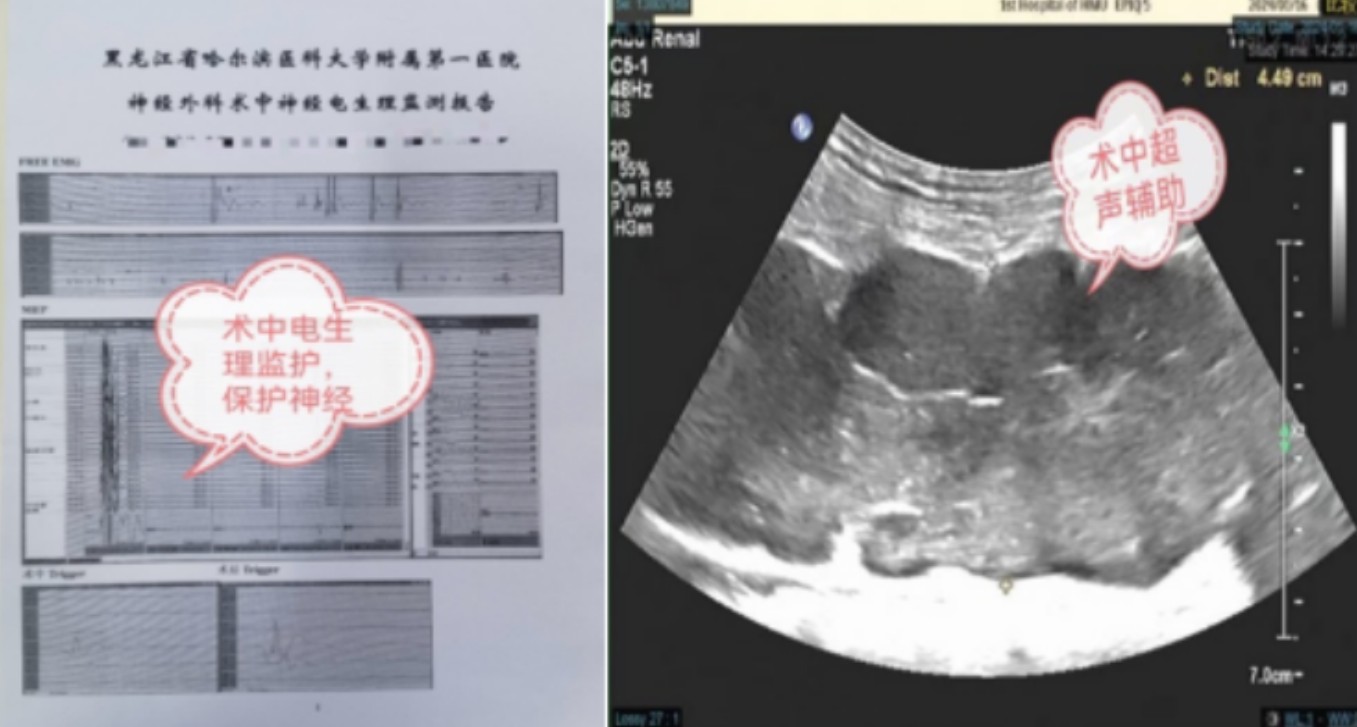

通过术中超声,拟定病变边界及切口范围:病变顶端位于左侧臀部,臀大肌深方,最低端达到膝盖下方外侧,总长近40厘米;术中通过神经外科显微镜,观察到病变附着在负责支配下肢运动的坐骨神经上,手术过程中稍有不慎就可能导致坐骨神经损伤,加重下肢活动障碍的情况。在电生理监测的保驾护航下,最大程度保护神经功能,仔细将神经分离,手术历经7个多小时,完整切除下肢巨大神经源性肿瘤。

可通过超声、核磁共振等方式进行检查,一旦确诊为周围神经神经肿瘤,首选的治疗方式为手术治疗,通过精细的手术操作,特别是在术中电生理及显微镜的辅助下,可以做到保留神经功能,避免术后出现神经功能障碍。

哈尔滨医科大学附属第一医院神经外科具有先进的显微外科设备,在术中电生理及术中超声的保驾护航下,影像科及手术室科学合理的协助下,为周围神经肿瘤的手术治疗提供一个良好的诊疗平台。